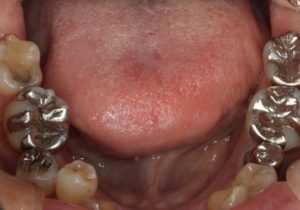

どのように変わったか、下の写真をご覧ください。

銀歯が多かったのですべて昔の銀歯の下もちりょうしながらセラミックにかえることができてとても満足しています。やっぱり白い歯よいですね。

治療お疲れ様でした。たくさん銀歯が入っていたのですが、最後には真っ白になりましたね。銀歯をやり直す材料にはセラミックとプラスティックがあるのですが、基本的にできるだけプラスティックで治すようにしています。この患者さんも、可能な限りプラスティックで治し、どうしても無理なところだけセラミックにしました。そのため歯を削る量が少ないことに加え、費用もかなり抑えることができます。たくさん治しましたが、全部セラミックで治さなければならないとなっていたら、もっともっと時間も費用もかかっていたかもしれません。当院では、初診時に治療方針や期間や費用などを1時間ほどかけて詳しく説明していますので、患者さんには治療内容について十分納得していただいていると考えています。「親身になって治療してくれる」とおっしゃっていただいたことは、そういったところを評価して頂いたのではいかと思っております。